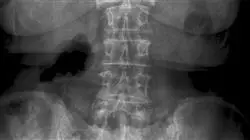

1.1.1. Изображение при торако-поясничных и крестцовых переломах

1.1.1.3. Управление и использование радиологической визуализации

1.1.1.4. Определить показания для соответствующего использования КТ или МРТ

1.5.1.1. Переломы позвонков с неврологическим поражением. Биомеханика. Критерии стабильности. Средства диагностики

1.5.1.2. Отличительная визуализационная диагностика травмы позвонков с неврологическим поражением